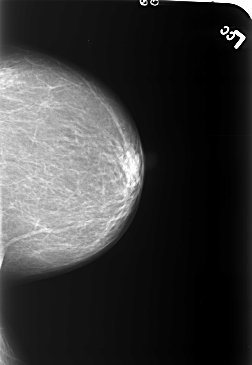

B_3233_1.LEFT_CC

LEFT_CC LINES 5464 PIXELS_PER_LINE 3768 BITS_PER_PIXEL 12 RESOLUTION 50 NON_OVERLAY